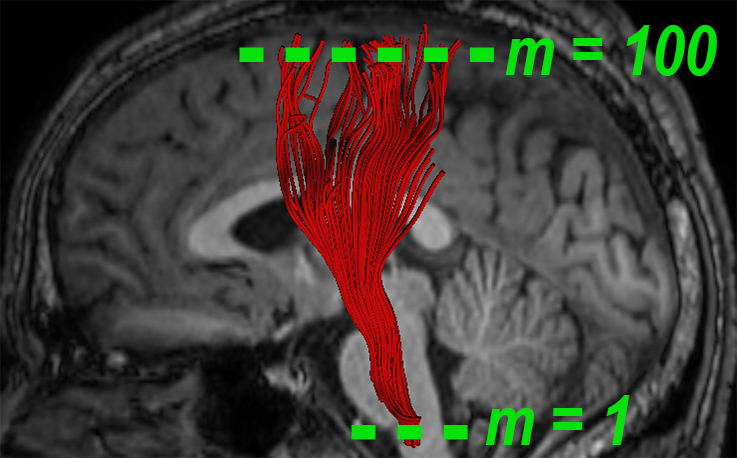

A fiber bundle can be thought of as a set of similar trajectories with a common origin and destination, along which water molecules are diffused [13]. In the spirit of this notion, we define a local measure for quantifying the fiber-flux of through a given plane , with normal at point , i.e.,

| (1) |

where is the number of intersected fibers, is the set of intersection points between the plane and the fiber bundle, and are the tangents of the fibers at those points. We call the fiber-flux density (FFD) of bundle at point . The plane is oriented such that the fiber-flux is maximized, i.e., . We use an iterative approach to solve this maximization problem in the spirit of [27]. We further introduce diffusivity properties into our model by extending the FFD measure. Let define a diffusivity scalar of choice (FA, MD, AD, or RD), associated with the point . We define the fiber-flux diffusion density (FFDD) as follows:

| (2) |

In practice, we refer to the FFDD as a vector to account for the local orientation of the fiber bundle. Note that the set of four FFDD descriptors (each assigned with a different diffusivity measure) couples diffusion measures with local geometrical features of the bundle. For example, local differences in orientation are taken into account, and regions with “incoherent” fiber orientations are “punished” by having lower FFDD values.

2.2 Along Tract Profiles

We calculate the mean fiber of the bundle , where is its arc-length parameter, based on Fourier descriptor [5]. According to this method, individual streamline fibers are represented by the coefficients of cosine series expansions, which are computed from tractography data using least squares estimation. The mean fiber is then optimally obtained by averaging the representation coefficients and applying the inverse transformation. The locations of the planar cross-sections along the bundle are determined by equidistant sampling points along the mean fiber . Tract-profiles are obtained by applying the FFDD descriptors along the tract, over these points.